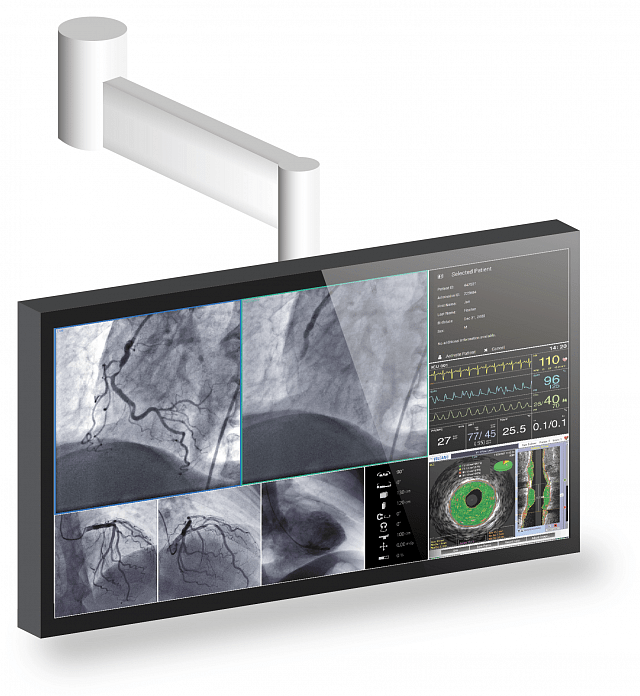

Der 55" Breitbild-Monitor mit 4K UHD Auflösung ist ideal für die Anzeige medizinischer Bilder in der Angiographie, Kardiologie oder Endoskopie geeignet und kann sowohl an der Wand als auch an eine Deckenhalterung montiert werden. Das Sicherheitskonzept und die langlebige Hintergrundbeleuchtung sind ideal für einen langfristigen, stabilen und verlässlichen Einsatz.

- Großer Blickwinkel durch IPS LCD Technologie.

- Schnelle Anpassung der Bilddarstellung an die Gegebenheiten vor Ort.

- Optimale Anzeige von DICOM Bildern durch Graustufenabgleich nach DICOM Part 14 Standard ab Werk.

- Hohe Funktionszuverlässigkeit durch redundate Komponenten im Gerät.

- Einheitliche Helligkeitsverteilung über den gesamten Schirm.